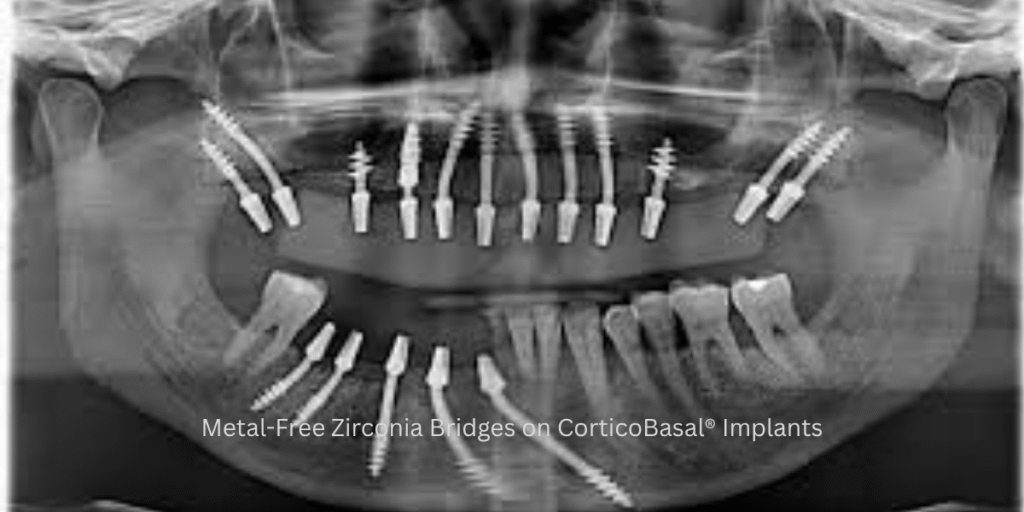

The real breakthrough comes from pairing zirconia bridges with CorticoBasal® Dental Implants in Delhi. Unlike conventional implants that require bone grafting or sinus lifts, CorticoBasal® Implants anchor directly into the cortical bone, enabling immediate loading of fixed teeth within 48 hours. For time-bound professionals, this means no prolonged waiting periods, no extended healing phases, and no disruption to their demanding schedules.

Zirconia bridges have emerged as a preferred alternative to traditional metal-based prosthetics because they offer unmatched strength, a natural tooth-like appearance, and superior biocompatibility. For working professionals who must maintain polished and confident smiles, zirconia eliminates the dull, metallic look of older restorations and provides long-lasting results without compromising aesthetics.